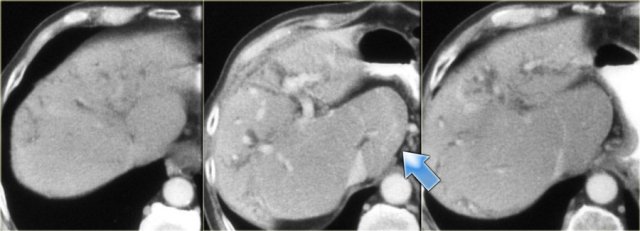

Late CT features are seen on the images on the left.

Study the images and then continue reading.

The findings are:

- Morphologic changes of cirrhosis (volume loss in the right lobe and a large caudate lobe (arrow)

- More pronounced dilatation of the bile ducts

On the left a typical case.

Notice the capsular retraction (blue arrow) and the late enhancement (yellow arrow).